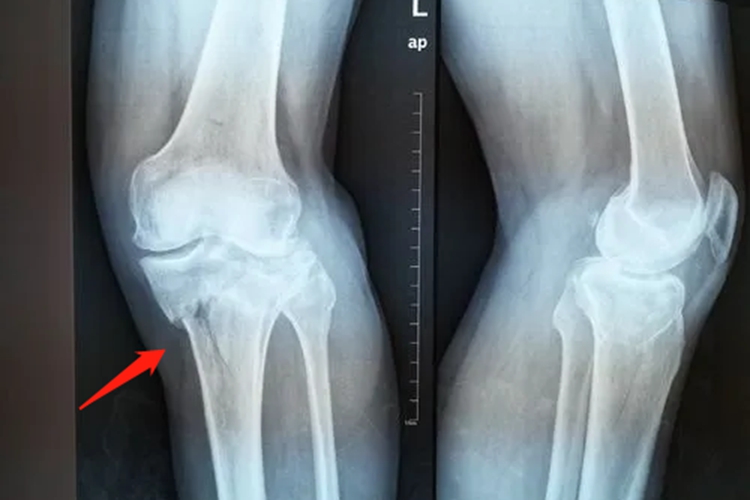

胫骨位于小腿内侧,其上端向两侧膨大,形成内侧髁和外侧髁,两髁上面有一关节面,即为胫骨平台,胫骨平台骨折又称胫骨髁骨折,好发于外髁,为关节内骨折。胫骨平台骨折后患膝会有肿胀、疼痛、活动障碍等表现,被动活动时膝关节疼痛,胫骨近端和膝部压痛明显。

胫骨平台骨折多是摔倒、高处坠落等间接暴力或高速撞击的直接暴力引起,骨折后需及时就诊,进行保守治疗,如闭合复位、骨牵引和石膏制动,必要时进行手术切开复位内固定治疗及植骨术。